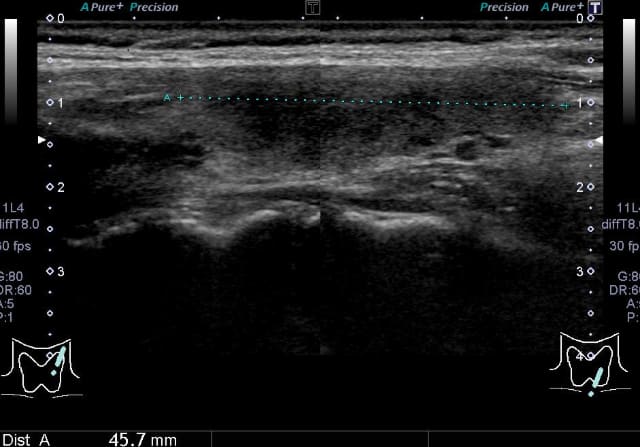

甲状腺超音波(エコー)検査では、甲状腺は基本的には全体的に大きくなり、内部は粗くみえることが多いです。臨床診断は、甲状腺の全体的な腫大に加えて、TgAbまたはTPOAb陽性で行います。甲状腺機能が正常であれば治療の必要はありません。機能が低下している場合には飲み薬(チラーヂンS®、レボチロキシン®)によって甲状腺ホルモンの補充を行います。服用は一日一回です。(吸収の安定性からは空腹時の服用がよく、また金属系製剤と同時服用は避ける必要があります)